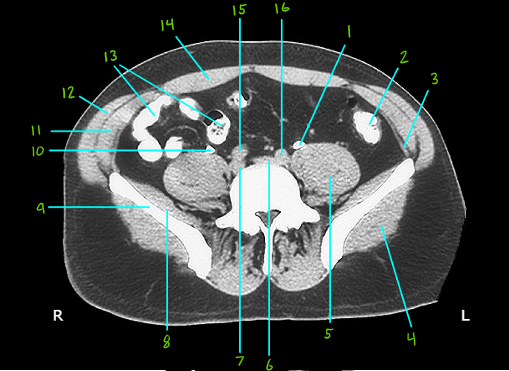

What is #1

Left ureter

What is #2

Sigmoid colon

What is #3

Transverse abdominis muscle

What is #4

Gluteus maximus muscle

What is #5

Posas major muscle

What is #6 & 7

R and L common iliac veins

What is #8

Iliacus muscle

What is #9

Ala of the illium

What is #10

Right ureter

What is #11

Internal oblique muscle

What is #12

External oblique muscle

What is #13

Ileum

What is #14

Rectus abdomins ,uscle

What is # 15 & 16

R and L commin iliac arteries